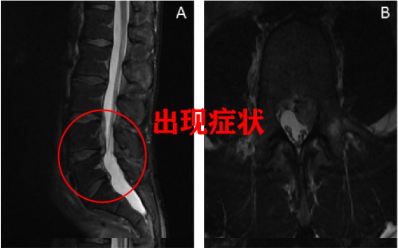

图一:LDH 患者 L4/5 在出现症状 5 个月后发生自发性消退

患者女,29 岁,因「右小腿疼痛并感觉异常」就诊,大小便正常。起始腰椎磁共振提示腰 L4/5 突出并椎管狭窄,神经根压迫严重(左图)。患者选择保守治疗,5 个月后复查 MRI(右图)发现突出的椎间盘自发性吸收了,并且临床症状基本缓解。